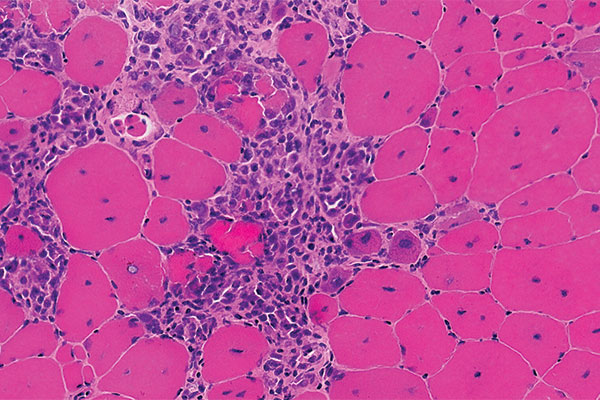

DMD is a genetic disease affecting about one in 3,500-5,000 male newborns worldwide. Because it decreases dystrophin protein in muscle tissues, it creates progressive weakness and challenges in everyday life. The DMD gene is the largest in the human genome, spanning 2.3 million base pairs (letters of DNA code) on the X chromosome. Most young boys are affected because the gene is on the X chromosome.